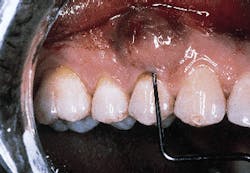

Photograph #3 is a view of a defect after thorough debridement. The periodontal disease process has resulted in an osseous dehiscence which extends 6 mm from the cementoenamel junction to the osseous crest on the mid-facial aspect of the involved premolar.

Photograph #3: This photograph demonstrates the root surface subsequent to degranulation and root debridement. Hand instruments and ultrasonic scalers were employed to detoxify the root surface.